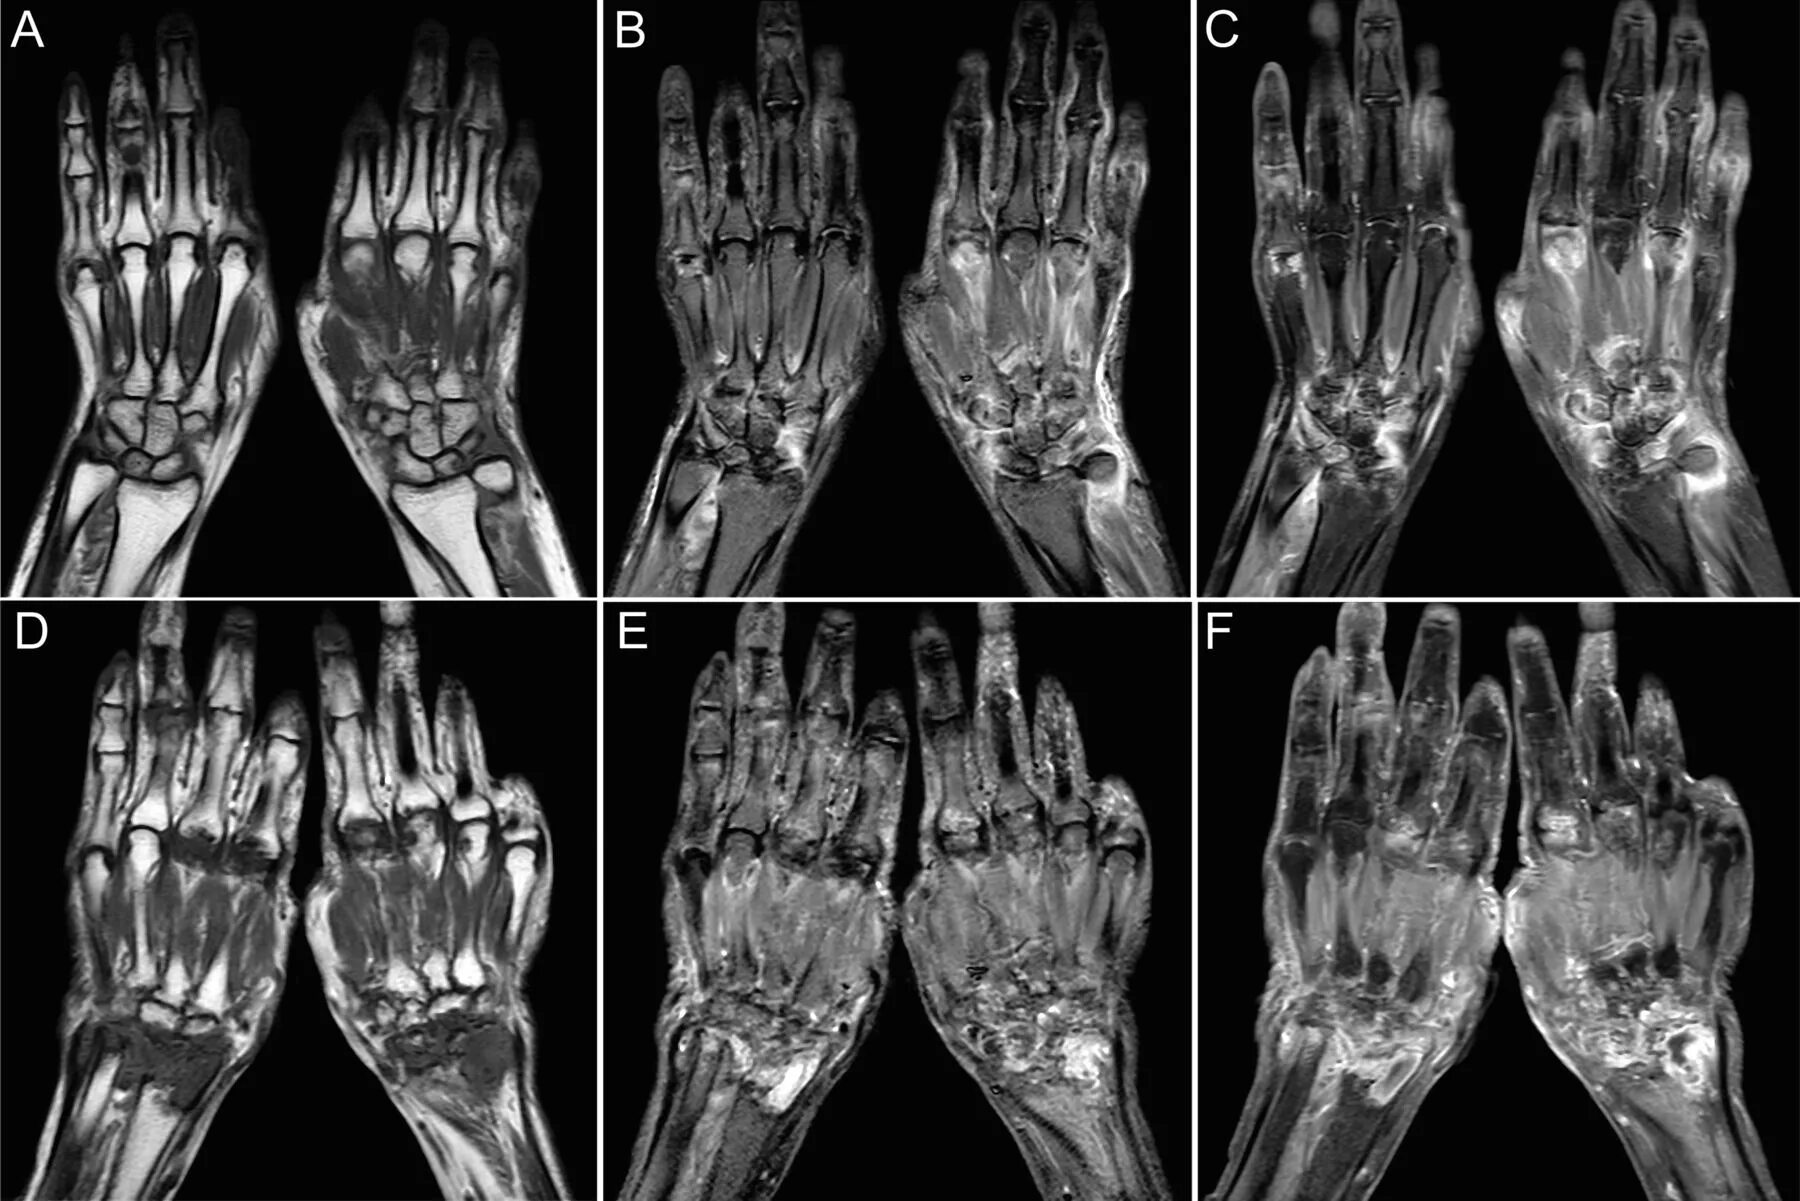

Кт суставов что показывает